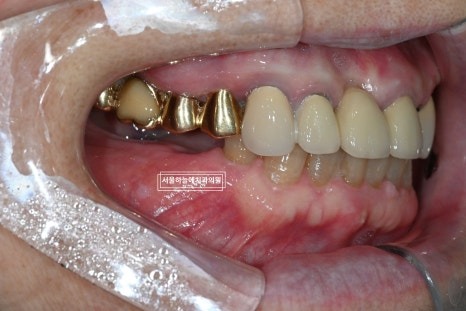

처음 내원 시 상태

처음 내원 당시 엑스레이와 구강 상태를 보면

앞니는 파절되어 있었고

아래 어금니가 없는 기간이 길어

위 치아와 잇몸이 맞닿을 정도로 공간이 부족,

아래 앞니 역시 심하게 마모된 상태였습니다.